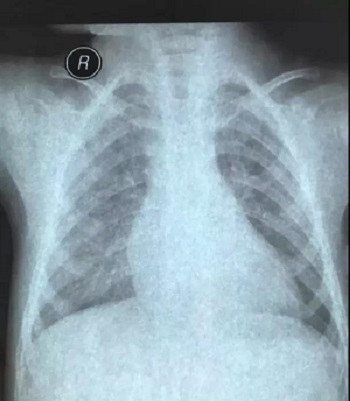

十二、拍摄时,尽可能的将片子上的文字信息拍摄清楚,并将左右拍摄清楚(片子上有标R,表示右侧right,L, 表示左侧left的意思), 每张片子上的文字都能按照阅读习惯拍正确,不要拍反了。

拍摄时,必须要对着片子上的文字对焦, 方向正确,将文字拍摄得清晰可视,保证放大图片后文字依然清晰可见(如下图),尽可能多的保留片子上的信息。